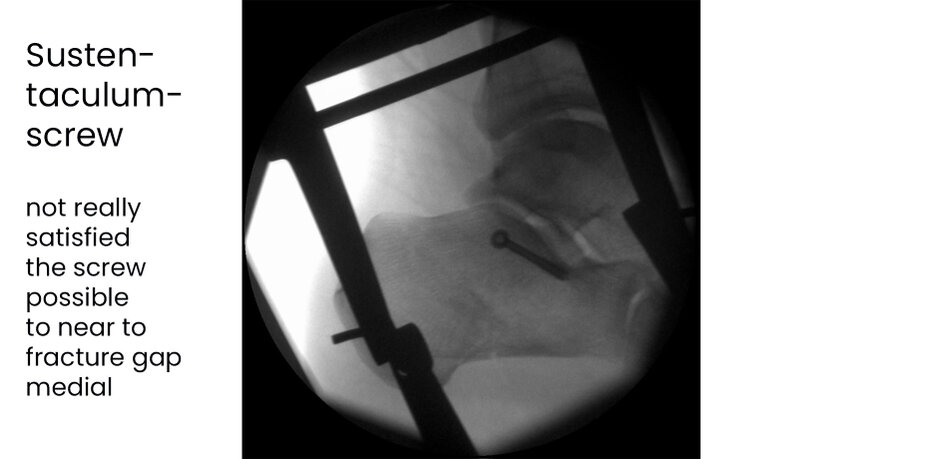

Case 17KL, male, 35y, surgery on day of trauma